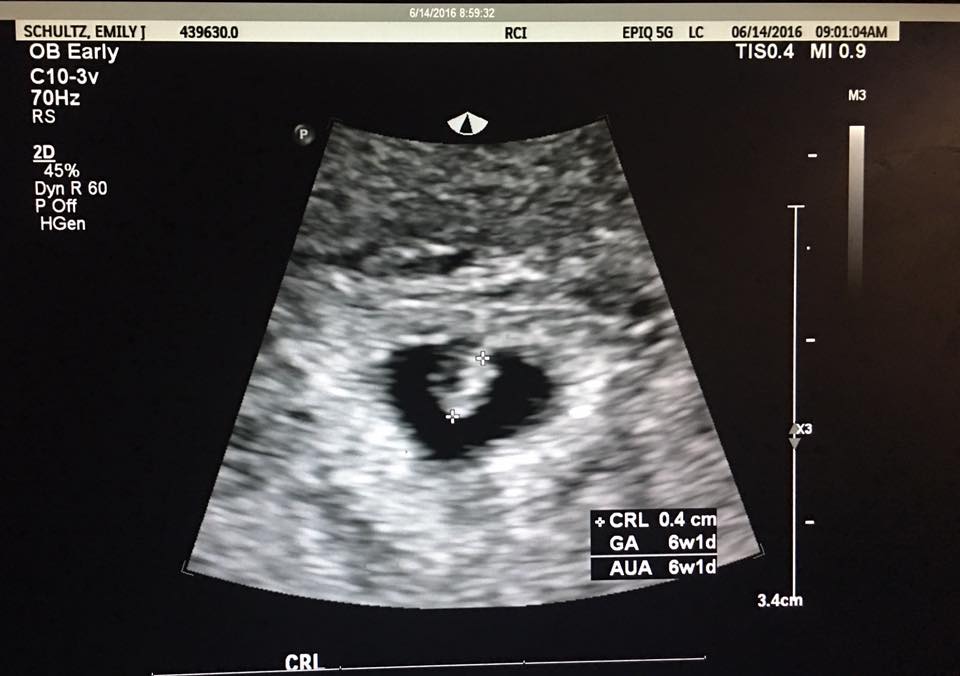

Anyone good at Ramzi method?? I have had four scans this pregnancy so far due to a SCH at 6, 7, 8, and today at 9+2. Just wondering your thoughts on this method, I know it's early and not 100% ;-)

Attachment 32033Attachment 32034Attachment 32035Attachment 32036